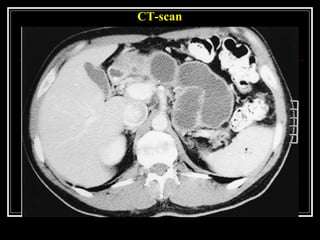

CT-scan

showing multiple, calcified intraductal stones in a patient with

chronic pancreatitis

CT-scan showing multiple, calcifiedintraductal stones in a patient with chronic pancreatitis